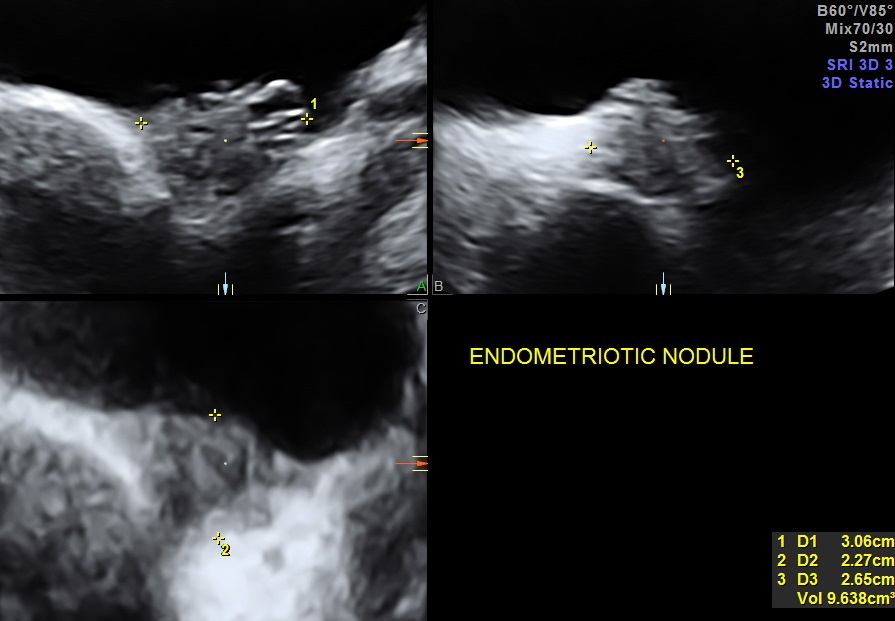

On evaluation she had a nodular swelling between the bladder and uterus. She had a few uro gynaecological consultations and cystoscopy and biopsy revealed endometriotic nodule. As she was reluctant to have any surgical correction , she was on conservative medical treatment . She also took hormonal treatment for endometriosis. The intensity of her symptoms reduced . She had come for her annual follow up scan and the pictures are given above.

The 3 D and 4D Live pictures of the endometriotic nodules are given above. The uro gynaecologist reviewed her and advised her to continue the conservative management.